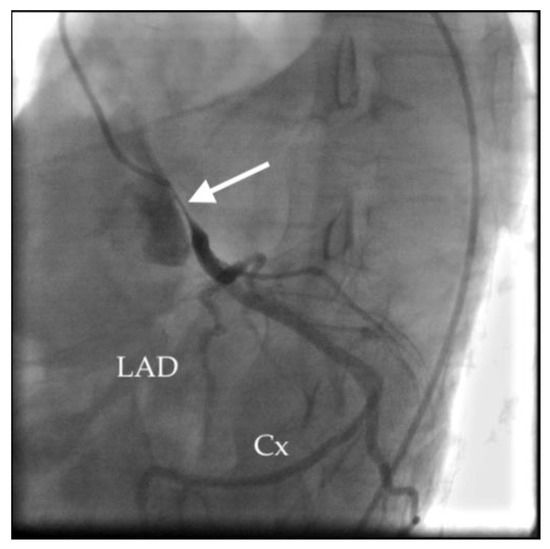

- Akbal, O.Y.; Kaymaz, C.; Tanboga, I.H.; Hakgor, A.; Yilmaz, F.; Turkday, S.; Dogan, C.; Tanyeri, S.; Demir, D.; Bayram, Z.; et al. Extrinsic Compression of Left Main Coronary Artery by Aneurysmal Pulmonary Artery in Severe Pulmonary Hypertension: Its Correlates, Clinical Impact, and Management Strategies. Eur. Heart J. Cardiovasc. Imaging 2018, 19, 1302–1308. [Google Scholar] [CrossRef]

- Caldera, A.E.; Cruz-Gonzalez, I.; Bezerra, H.G.; Cury, R.C.; Palacios, I.F.; Cockrill, B.A.; Inglessis-Azuaje, I. Endovascular Therapy for Left Main Compression Syndrome. Case Report and Literature Review. Chest 2009, 135, 1648–1650. [Google Scholar] [CrossRef]

- Galiè, N.; Saia, F.; Palazzini, M.; Manes, A.; Russo, V.; Bacchi Reggiani, M.L.; Dall’Ara, G.; Monti, E.; Dardi, F.; Albini, A.; et al. Left Main Coronary Artery Compression in Patients With Pulmonary Arterial Hypertension and Angina. J. Am. Coll. Cardiol. 2017, 69, 2808–2817. [Google Scholar] [CrossRef]